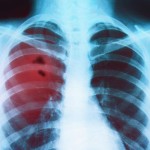

Q Fever

Q fever can cause acute or chronic illness in humans, who usually acquire the infection after contact with infected animals or exposure to contaminated environments. The acute symptoms caused by infection with Coxiella burnetii usually develop within 2-3 weeks of exposure, although as many as half of humans infected with C.burnetii do not show symptoms. Symptoms The following is a list of symptoms commonly seen with acute Q fever. Howe. Read more...